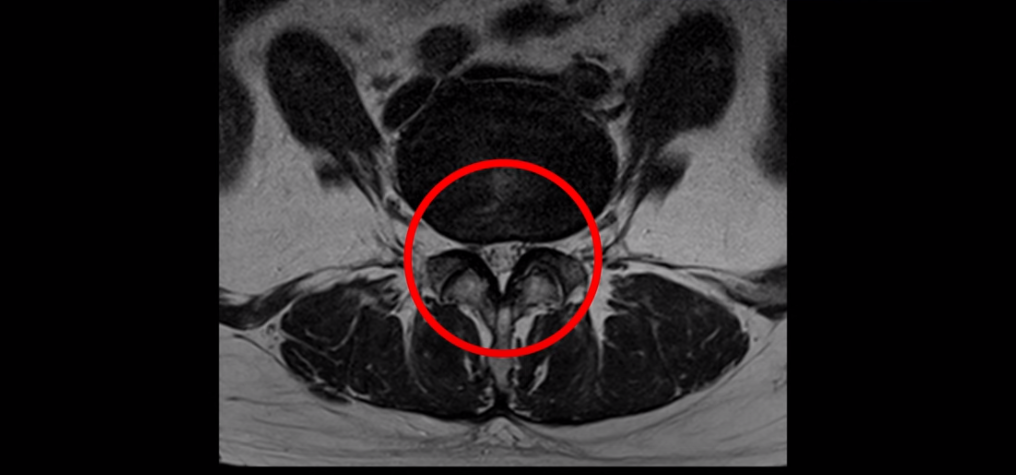

또 4번 5번 마디에 오른쪽으로 찢어져서 밀려나온 디스크 탈출이 보입니다.

밀려나온 수핵이 조금 흘러내려 있습니다.